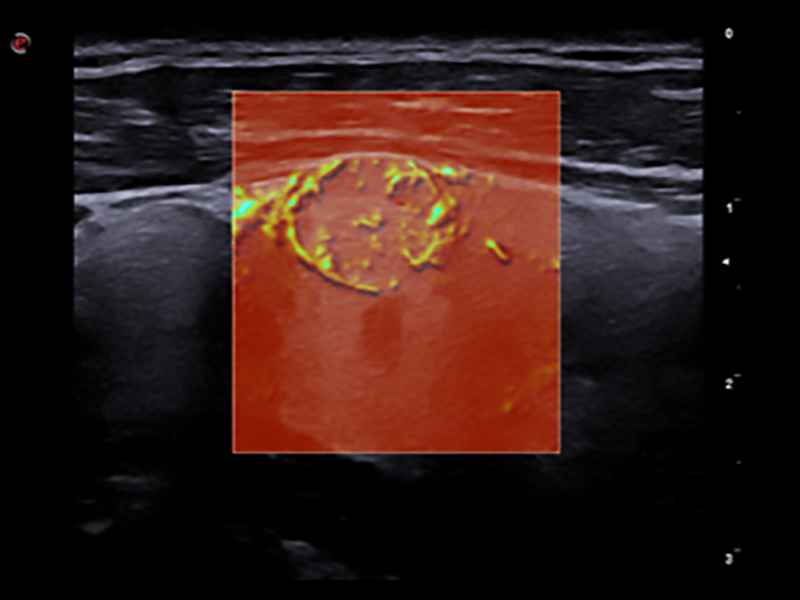

Doppler technology, with high sensitivity, is essential in any inflammation process where it is crucial to analyse slow flows.

The extreme sensitivity of Esaote Power Doppler technology is designed for the detection of low flow in small and superficial vessels. This improved vascular image quality, provided by Esaote, has positive impacts on diagnosis and therapy planning. Moreover, Esaote pushes the limits of microvascularization imaging one step further, with the latest implementation of microV technology to detect the smallest flow, bringing precious clinical value in the early detection, diagnosis and follow-up of musculoskeletal injuries or lesions characterization. Thanks to BrightFlow Technology, 3D rendering can be applied to all colour modalities to enhance vessel visualization.